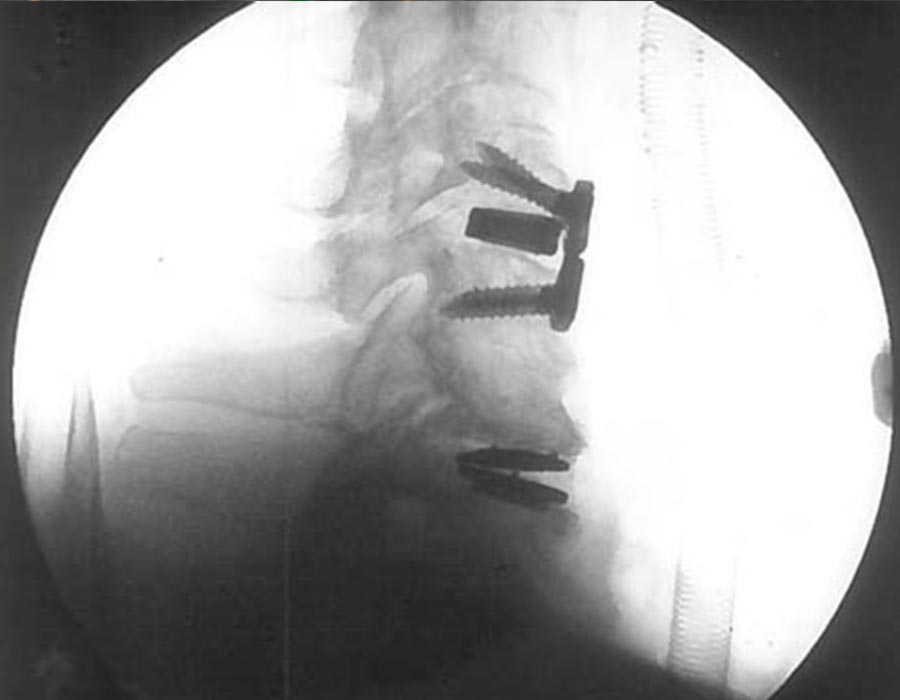

• Discectomía anterior C4-C5 y artrodesis intersomática con PEEK titanio e injerto autólogo y placa ABC , añadiendose Cobertura dural con Lyoplant

• Discectomía anterior C6-C7. Foraminotomía bilateral/barras osteofitarias y artroplastia C6-C7 Activ C

• Se objetiva control radiológico satisfactorio.

cirugia avanzada de columna cervical